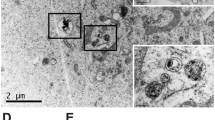

P-CQD NPs and biodistribution

To investigate bio-distribution, CQDs were applied. TEM images of CQDs indicated that the CQDs were semi-spherical with a size range below 10 nm (mean = 3.57 ± 1.9 nm) (Fig. 10A). Emission spectra of the CQD were around 400–500 nm (Fig. 10D), and the crystalline structure of the CQDs was assayed via XRD. Interlayer spaces were confirmed by the existence of a wide peak at 22 degrees at 3.39 Å (Fig. S9C)73,74. FTIR results showed bands at 1120, 1390, and 1720 cm-1 which are from the stretching vibration of C–O75, O–H74, and C = O76 functional groups and also peaks at 3100 and 3400 cm-1 which are due to the stretching vibration of –NH77 and –OH78 groups. These functional groups are pursuant to the elements in the CQDs structure (Fig. S9A)74.

(A) TEM image of CQD (Scale bar = 10 nm), (B) SEM image of P-CQD NPs (Scale bar = 100 nm), (C) in vitro release profile of CQD from P-CQD NPs data = mean ± SD, n = 5, (D) emission spectra of CQD, (E) schematic image of P-CQD NPs, (F) fluorescent bio tracking of P-CQD NPs 1, 6, 24, and 48 h after IV injection, (G) fluorescent intensity of dissected organs after 48h, (H) fluorescent intensity of injected sample (before injection), (I) average signal count emitted from each organ, (Data = mean ± SD) and (J) percent of signal count in organs, (Data = mean ± SD, *P < 0.05, **P < 0.01, ***P < 0.001, ****P < 0.0001).

After making sure the CQDs were suitable, P-CQD NPs were prepared. Since these NPs can stimulate the biodistribution of P-MTX NPs and P-PTX NPs in the body, it was necessary to have similar physiochemical properties. The P-CQD NPs hydrodynamic size was 150 ± 23 nm with a zeta potential of −27.3 ± 0.6 mV, which was relatively similar to P-MTX NPs and P-PTX NPs. SEM images showed semi-spherical NPs with a rough surface that may be because of the adherence of the CQDs on the surface of the NPs (Fig. 10B). The in vitro release of CQDs from P-CQD NPs was also studied to ensure that these NPs are suitable for biodistribution studies lasting up to 48 h. In vitro release results showed that only 30% of the loaded CQDs were released from the NPs during the first 48 h (Fig. 10C). Therefore, we can conclude that most of the adsorption intensity in the biodistribution study was related to the distribution of the NPs, not free CQDs. Figure 10 E is a schematic view of P-CQD NPs applied for the biodistribution studies.